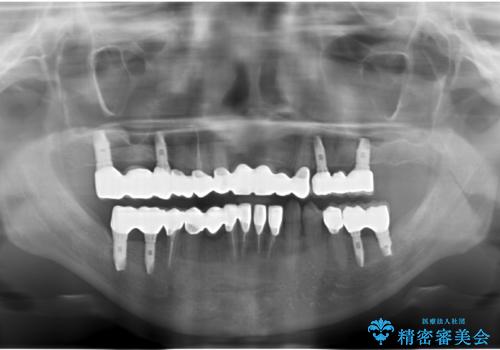

歯周病 全顎治療

- 前歯の見た目、入れ歯による噛めないことの改善を求めて来院されました。

検査により全顎的な歯周病治療、欠損のインプラント補綴、根管治療が必要な状態であることをお伝えし、治療を計画します。

失ってしまった機能を回復し、今後歯を失わないよう残せる歯に歯周病治療を行い、安定した咬合を確立することで長期的に問題なく噛めるような口腔内環境を達成できるようになると考えます。